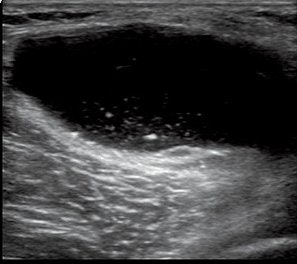

![]() |

| Baker's cyst is one of the risk factors of painful flare in OA of the knee. These patients show a tendency to have an increased rate of Baker's cyst on ultrasonographic findings (Osteoarthritis and Cartilage, June 2006, Vol. 14:6, pp. 540-544). Image courtesy of GE Healthcare. |